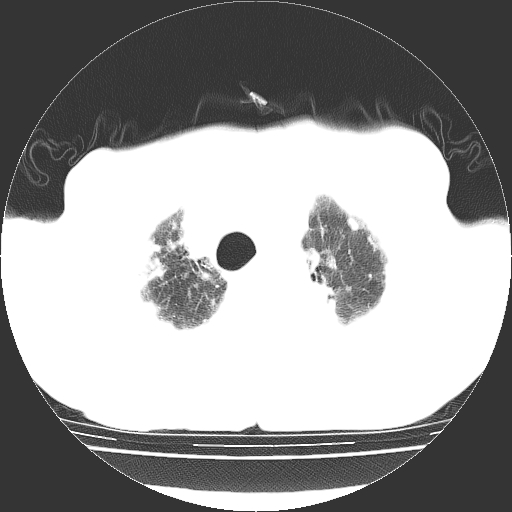

标题: CT25149:男,69岁,反复咳嗽、咳痰五年余,呼吸困难三天。 [打印本页]

男,69岁,反复咳嗽、咳痰五年余,呼吸困难三天。

慢支伴感染、肺气肿、肺心病

慢支伴感染、肺气肿、肺心病!支持!另:间质纤维化!

慢支伴感染、肺气肿、肺心病。双肺间质性改变(间质纤维化)。